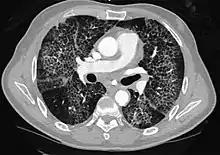

CT image showing diffuse GGOs throughout both lungs. An abscess is also noted in the right lung (screen left). - Adenocarcinoma in situ of the lung

Diffuse

The diffuse pattern typically refers to GGOs in multiple lobes of one or both lungs. Broadly, a diffuse pattern of GGO can be caused by displacement of air with fluid, inflammatory debris, or fibrosis. Cardiogenic pulmonary edema and ARDS are common causes of a fluid-filled lung. Diffuse alveolar hemorrhage is a rarer cause of diffuse GGO seen in some types of vasculitis, autoimmune conditions, and bleeding disorders.[6]

Inflammation and fibrosis can also cause diffuse GGOs. Pneumocystis pneumonia, an infection typically seen in immunocompromised (e.g. patients with AIDS) or immunosuppressed individuals, is a classic cause of diffuse GGOs. Many viral pneumonias and idiopathic interstitial pneumonias can also lead to a diffuse GGO pattern. Radiation pneumonitis, a side effect of pulmonary radiation therapy, can lead to pulmonary fibrosis and diffuse GGOs.[6]